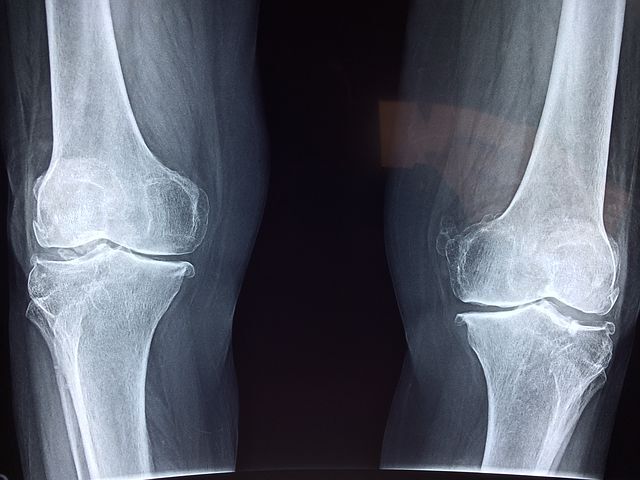

손이나 발가락 같은 작은 관절에 발병하는 경우가 많다고 볼수 있지만, 기간이 길어지면서 무릎이나 어깨ㆍ허리 등의 큰 관절에 염증이 전이되는 경우가 대부분입니다. 아직까지 왜 이런 증상들이 일어나는지 완벽하게 밝혀지지는 않았지만, 유전 적 요인과 흡연 습관, 잇몸 질환과 관련이 있다고 보고되고 있습니다.

류마티스 관절염 증상 초기에는 좌우 대칭으로 손가락과 발가락의 관절이 붓고, 아침에 경직을 느끼게 일반적이라 할수 있습니다. 시간이 흐름에따라 관절이 파괴되면, 작은 관절도 생활에 큰 불편함을 초래하게 되는 것입니다.

또한 환자는 무릎 관절이나 엉덩이 등 하체의 큰 관절에까지 영향을 미칠수있고, 걸음이 현저하게 곤란해질 수 있습니다.